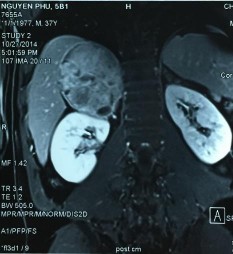

Phim MRI bướu tuyến thượng thận 2 bên

Bệnh phẩm bướu sắc bào tủy TTT bên trái

Phim MRI sau phẫu thuật cắt bướu TTT bên trái

[Nguyễn P., 37 tuổi, SNV: 214061952]